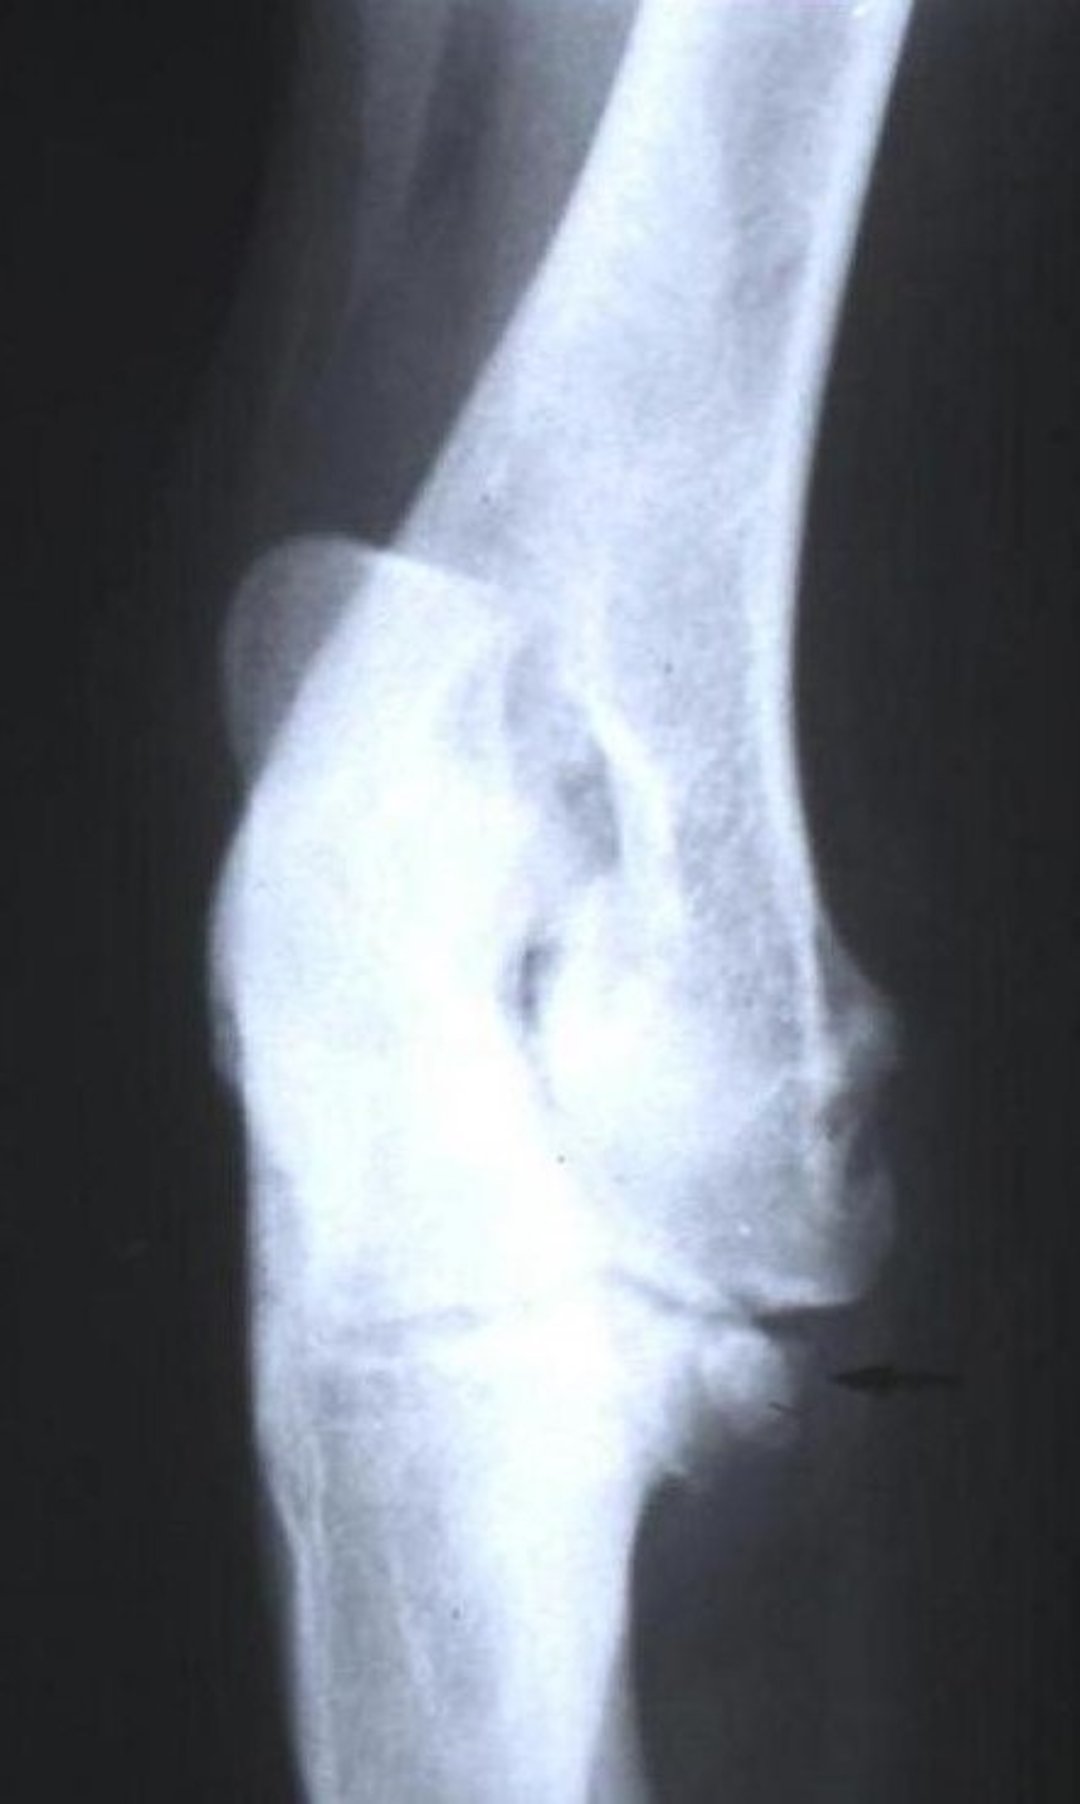

In chronic cases of UAP, muscle atrophy can occur. Some animals show external rotation of the limb or abduction of the elbow. UAP is suggested by these clinical signs, as well as by radiographic evidence. A lateral radiograph of the elbow in a fully flexed position enables visualization of the ununited process. Both elbows should be examined, because the condition can be bilateral. CT can confirm the diagnosis.

Some large breeds of dogs (German Shepherd Dog, Saint Bernard, Basset Hound, etc) have a secondary center of ossification for the anconeal process. Fusion should be completed by the age of 5–6 months. In ununited anconeal process (UAP), this fusion fails (see UAP image), resulting in a more or less mobile fragment that causes joint instability, pain, inflammation, and eventually osteoarthritis (OA).

UAP occurs when the anconeal process fails to fuse with the ulna at the correct age, maintaining a fibrous tissue connection. This instability creates a pseudarthrosis at the growth center site, serving as an important primary cause of severe OA.